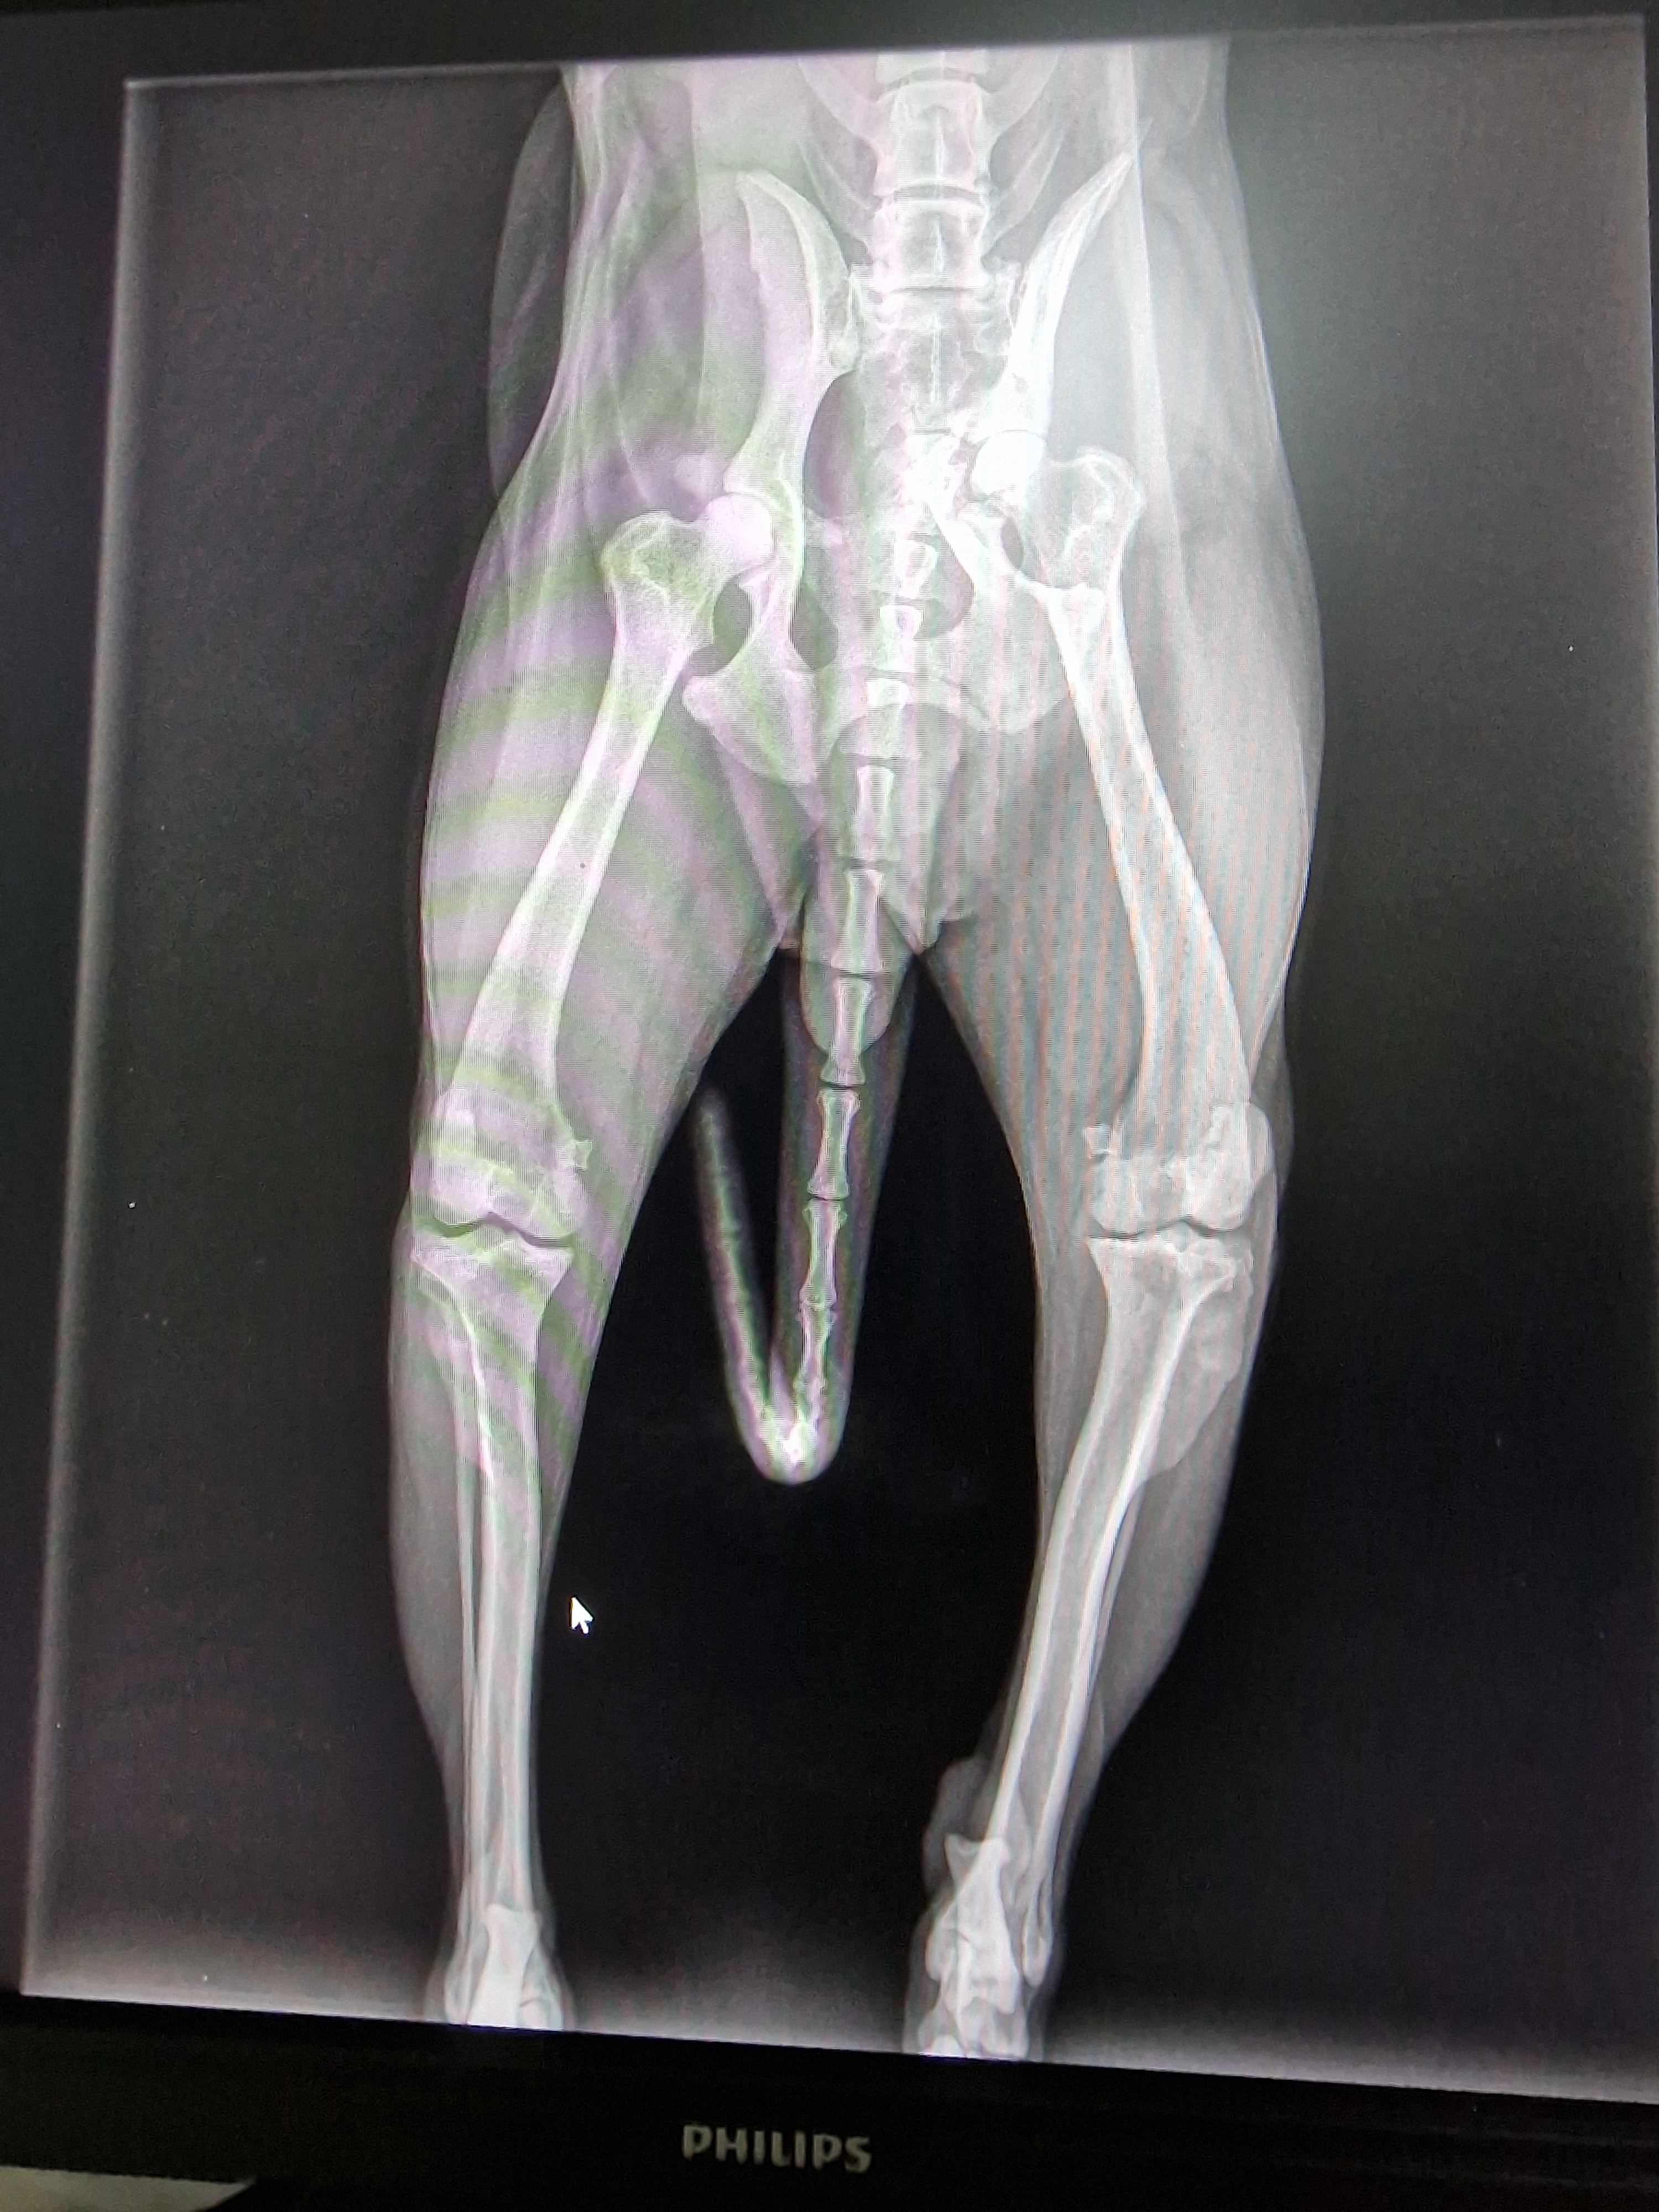

Ho poi scoperto che ti chiami Bianca, che hai 10 anni, mai sterilizzata, sempre a caccia. L'ultima volta ti sei persa nei boschi e ti hanno ritrovata in una scarpata, investita . Hai fatto un bel volo con conseguente frattura del femore . Sei rimasta immobile li sotto...

Per adesso ho bisogno di aiuto per farla operare , un osteoctomia alla testa e al collo del femore.